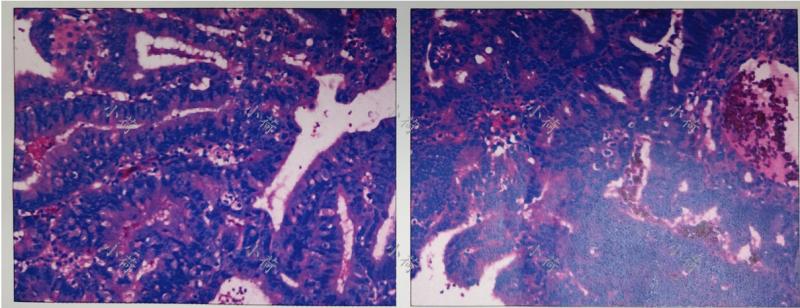

术后病理提示:子宫内膜样癌Ⅱ~Ⅲ级伴区域性神经内分泌癌分化,侵及肌层>1/2,宫颈内口受侵,宫颈外切缘阴性,卵巢子宫内膜样腺癌(图2)。术后诊断为:子宫内膜样腺癌Ⅲ期。

图2 术后病理图片